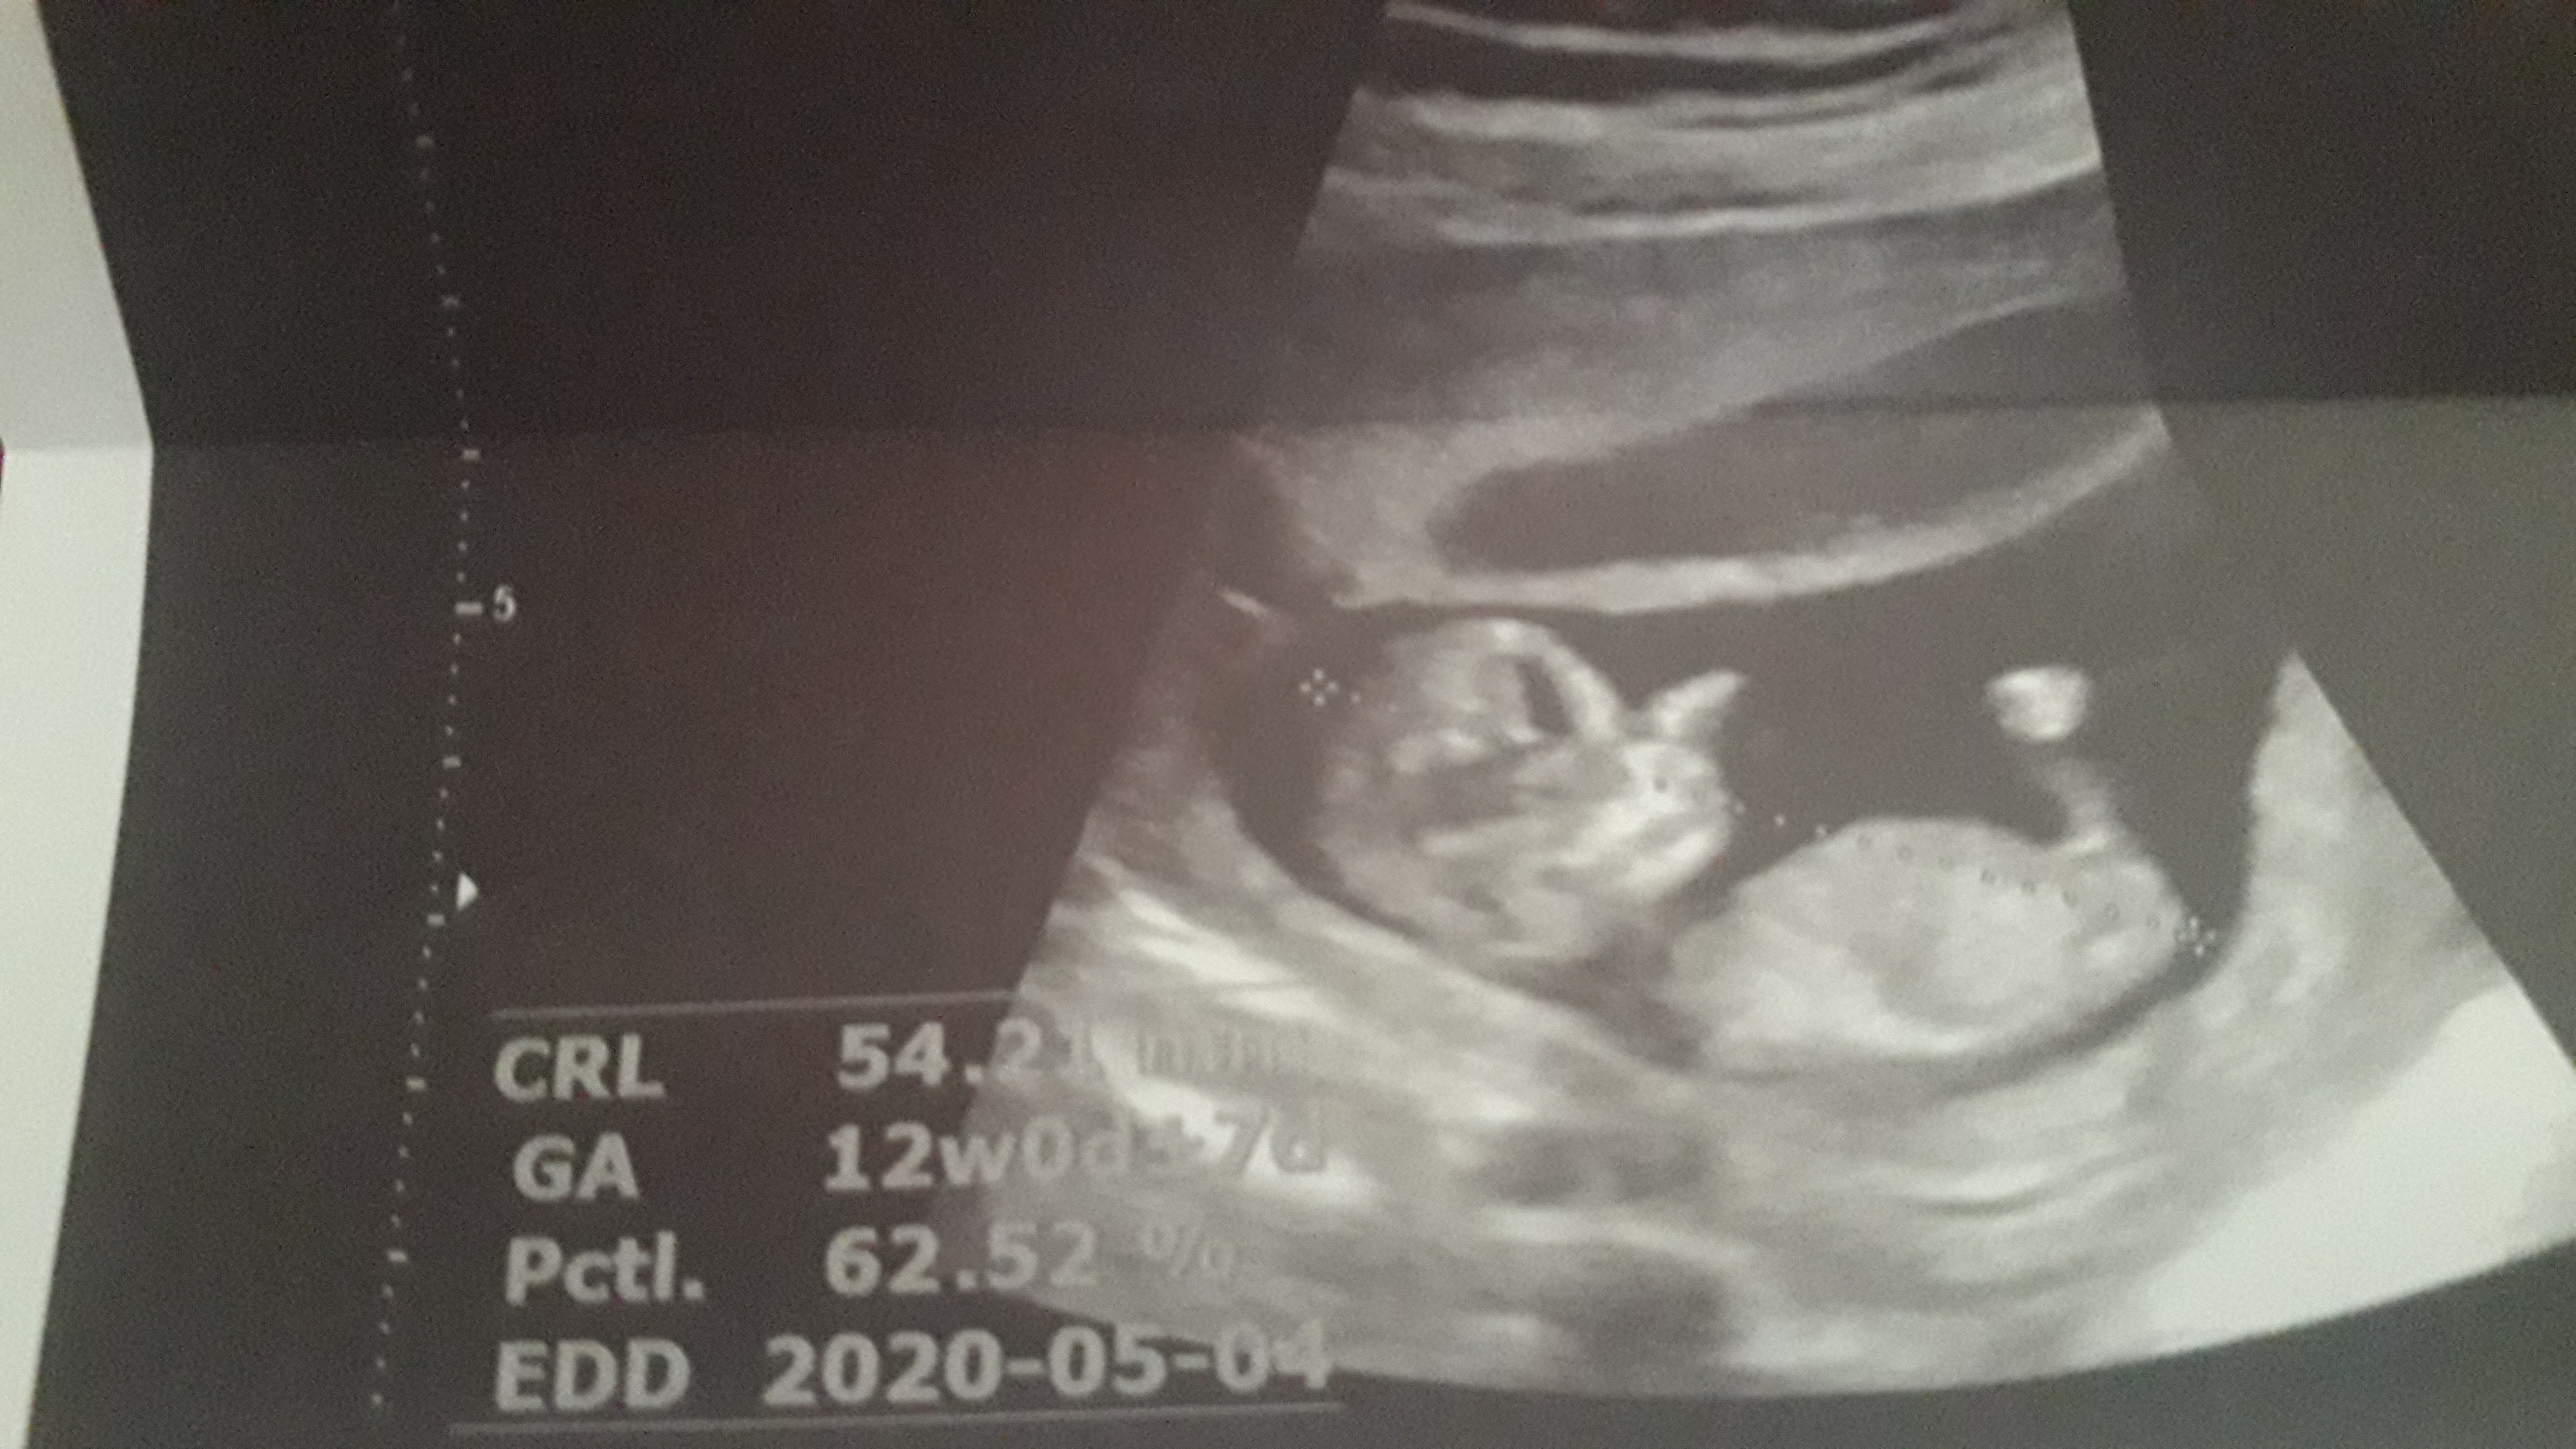

anya_95 عضویت: 1398/05/18 تعداد پست: 1136 ای جانم دوقلو😍فک کنم هردو دخترن ولی عکس دومیو یکم شک دارم ❤میشه واسه سلامتی گل پسرم ی صلوات مهمونم کنی❤مرسی مهربونا😘